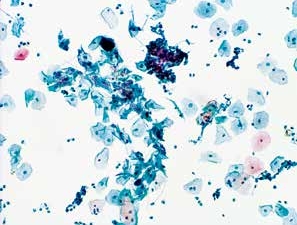

1. 细菌性阴道病(bacterial vaginosis)(图2-1~2-3)

图2-1 细菌性阴道病(高倍、液基、巴氏染色)

鳞状上皮细胞表面覆盖着许多细菌(主要为球菌),嗜碱性,细胞模糊不清,似有薄膜遮盖,这种特殊形态的细胞称为线索细胞。

细菌性阴道病是最常见的妇科感染,主要由于乳酸杆菌缺乏导致阴道pH值增加,使其他球菌或杆菌得以生长。朦胧的背景,小的球状杆菌,鳞状细胞表面覆盖着许多细菌,主要为球菌,嗜碱性,使细胞表面和细胞轮廓模糊不清,像有薄膜覆盖,这种特殊形态的细胞称为线索细胞(clue cells)。显微镜下查见线索细胞,报告菌群失调,提示细菌性阴道病。